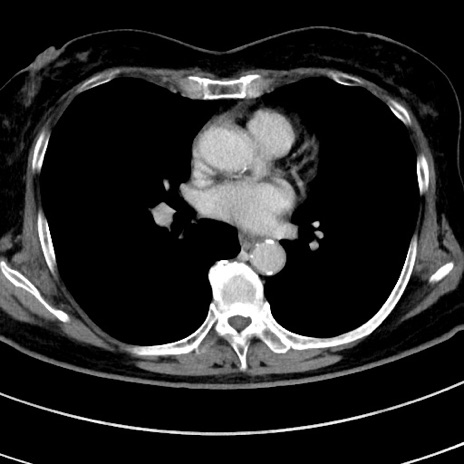

症例9(横断像)

【症例】 60歳代女性

【主訴】むかつき、みぞおちの痛み

【現病歴】3日前よりむかつきがあり、食事がとれない。

【既往歴】糖尿病

【身体所見】発熱なし、心窩部圧痛軽度あるも、腹膜刺激症状なし。

【データ】WBC 7400、CRP 1.92